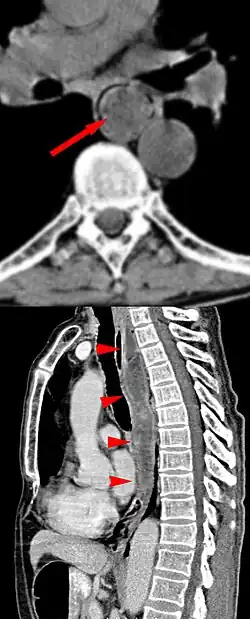

Die Röntgenbreischluckuntersuchung zeigt einen langen, keulenförmigen, umspülten, intraluminalen Tumor mit glatter, etwas gelappter Kontur. Bei einem sehr voluminösen Tumor kann der erweiterte Ösophagus in der Röntgenaufnahme des Thorax für das Mediastinum konturbildend werden.

Wenn der Tumor eindeutig Fett enthält, ist dieses in der Computertomographie oder Kernspintomographie nachweisbar und kann so zur Abgrenzung gegen andere Tumoren hilfreich sein.